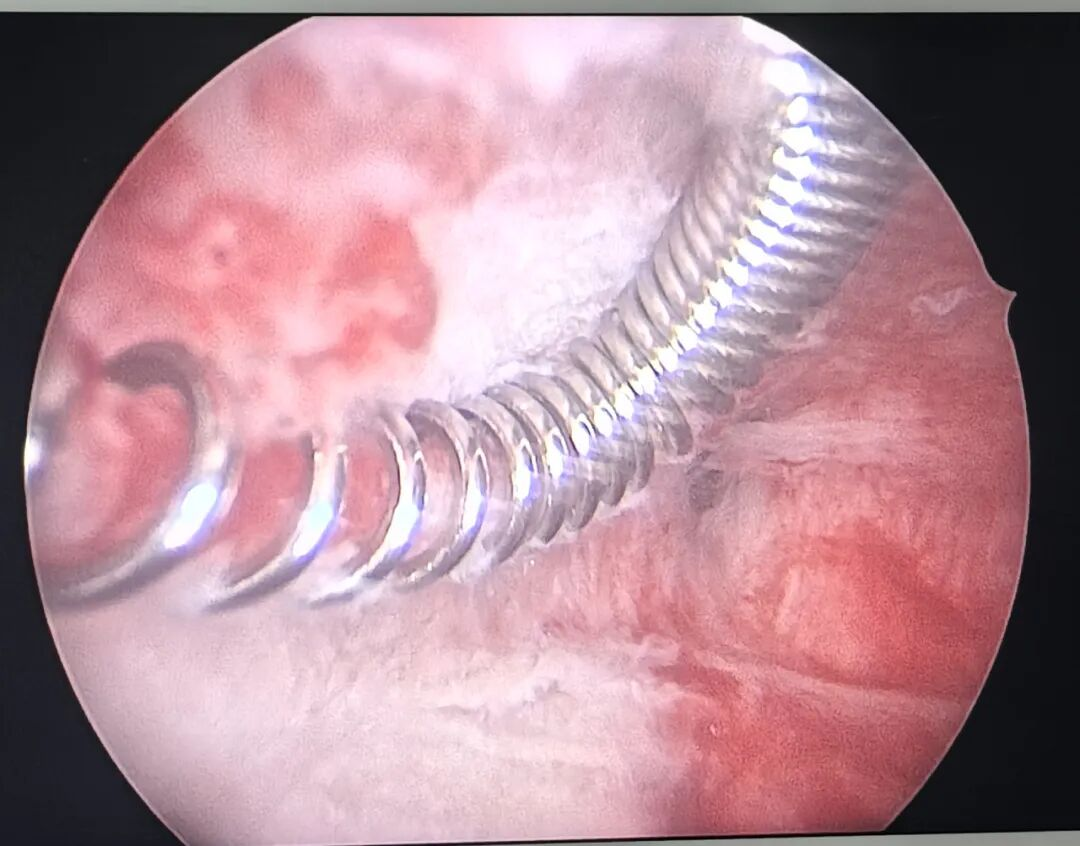

▲节育环被黏连带包裹

▲剪开黏连带后

术中发现患者因绝经导致生殖道萎缩,显著增加了手术难度。面对阴道狭窄、宫颈扩张困难等问题,我院省医派驻专家、妇产科副主任马啸与曾秋兰副主任医师在尝试常规取环方法未能成功之后,转而借助宫腔镜进行反复探查,发现节育环被一层黏连带紧密包裹于宫腔右侧壁。经团队讨论,决定采用宫腔镜剪刀剪开黏连带。尽管手术过程中因宫腔体积缩小、宫颈组织变硬面临诸多挑战,但凭借耐心细致的操作,最终顺利取出节育环并一并切除了内膜息肉。